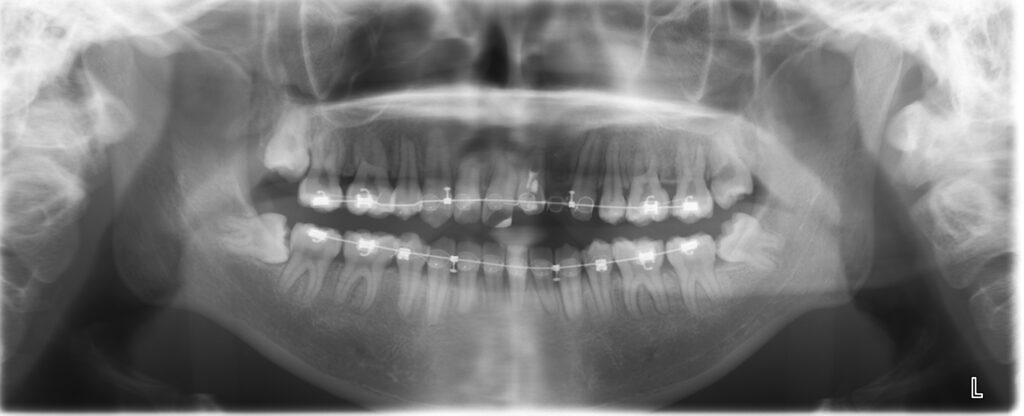

この画像をみてください。

よくある歯列矯正ですが、

この矯正治療をしている歯科医院のウリは

他院よりも急速矯正であるということ。通常の半分の時間で

歯列矯正が済むというお話だそうです。

いかにも強そうな針金ですね(笑)

反対側です。

上から

下から

いかにもガッチリです。